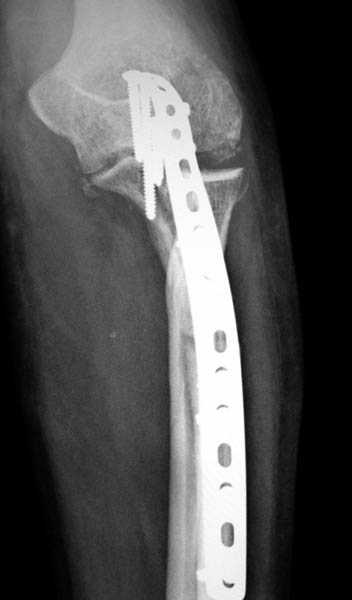

Здесь выставлены несколько случаев и варианты фиксации локтевого отростка, некоторые в комбинации с другими переломами.

1 вариант применен ACUMED локинг пластина

2 вариант